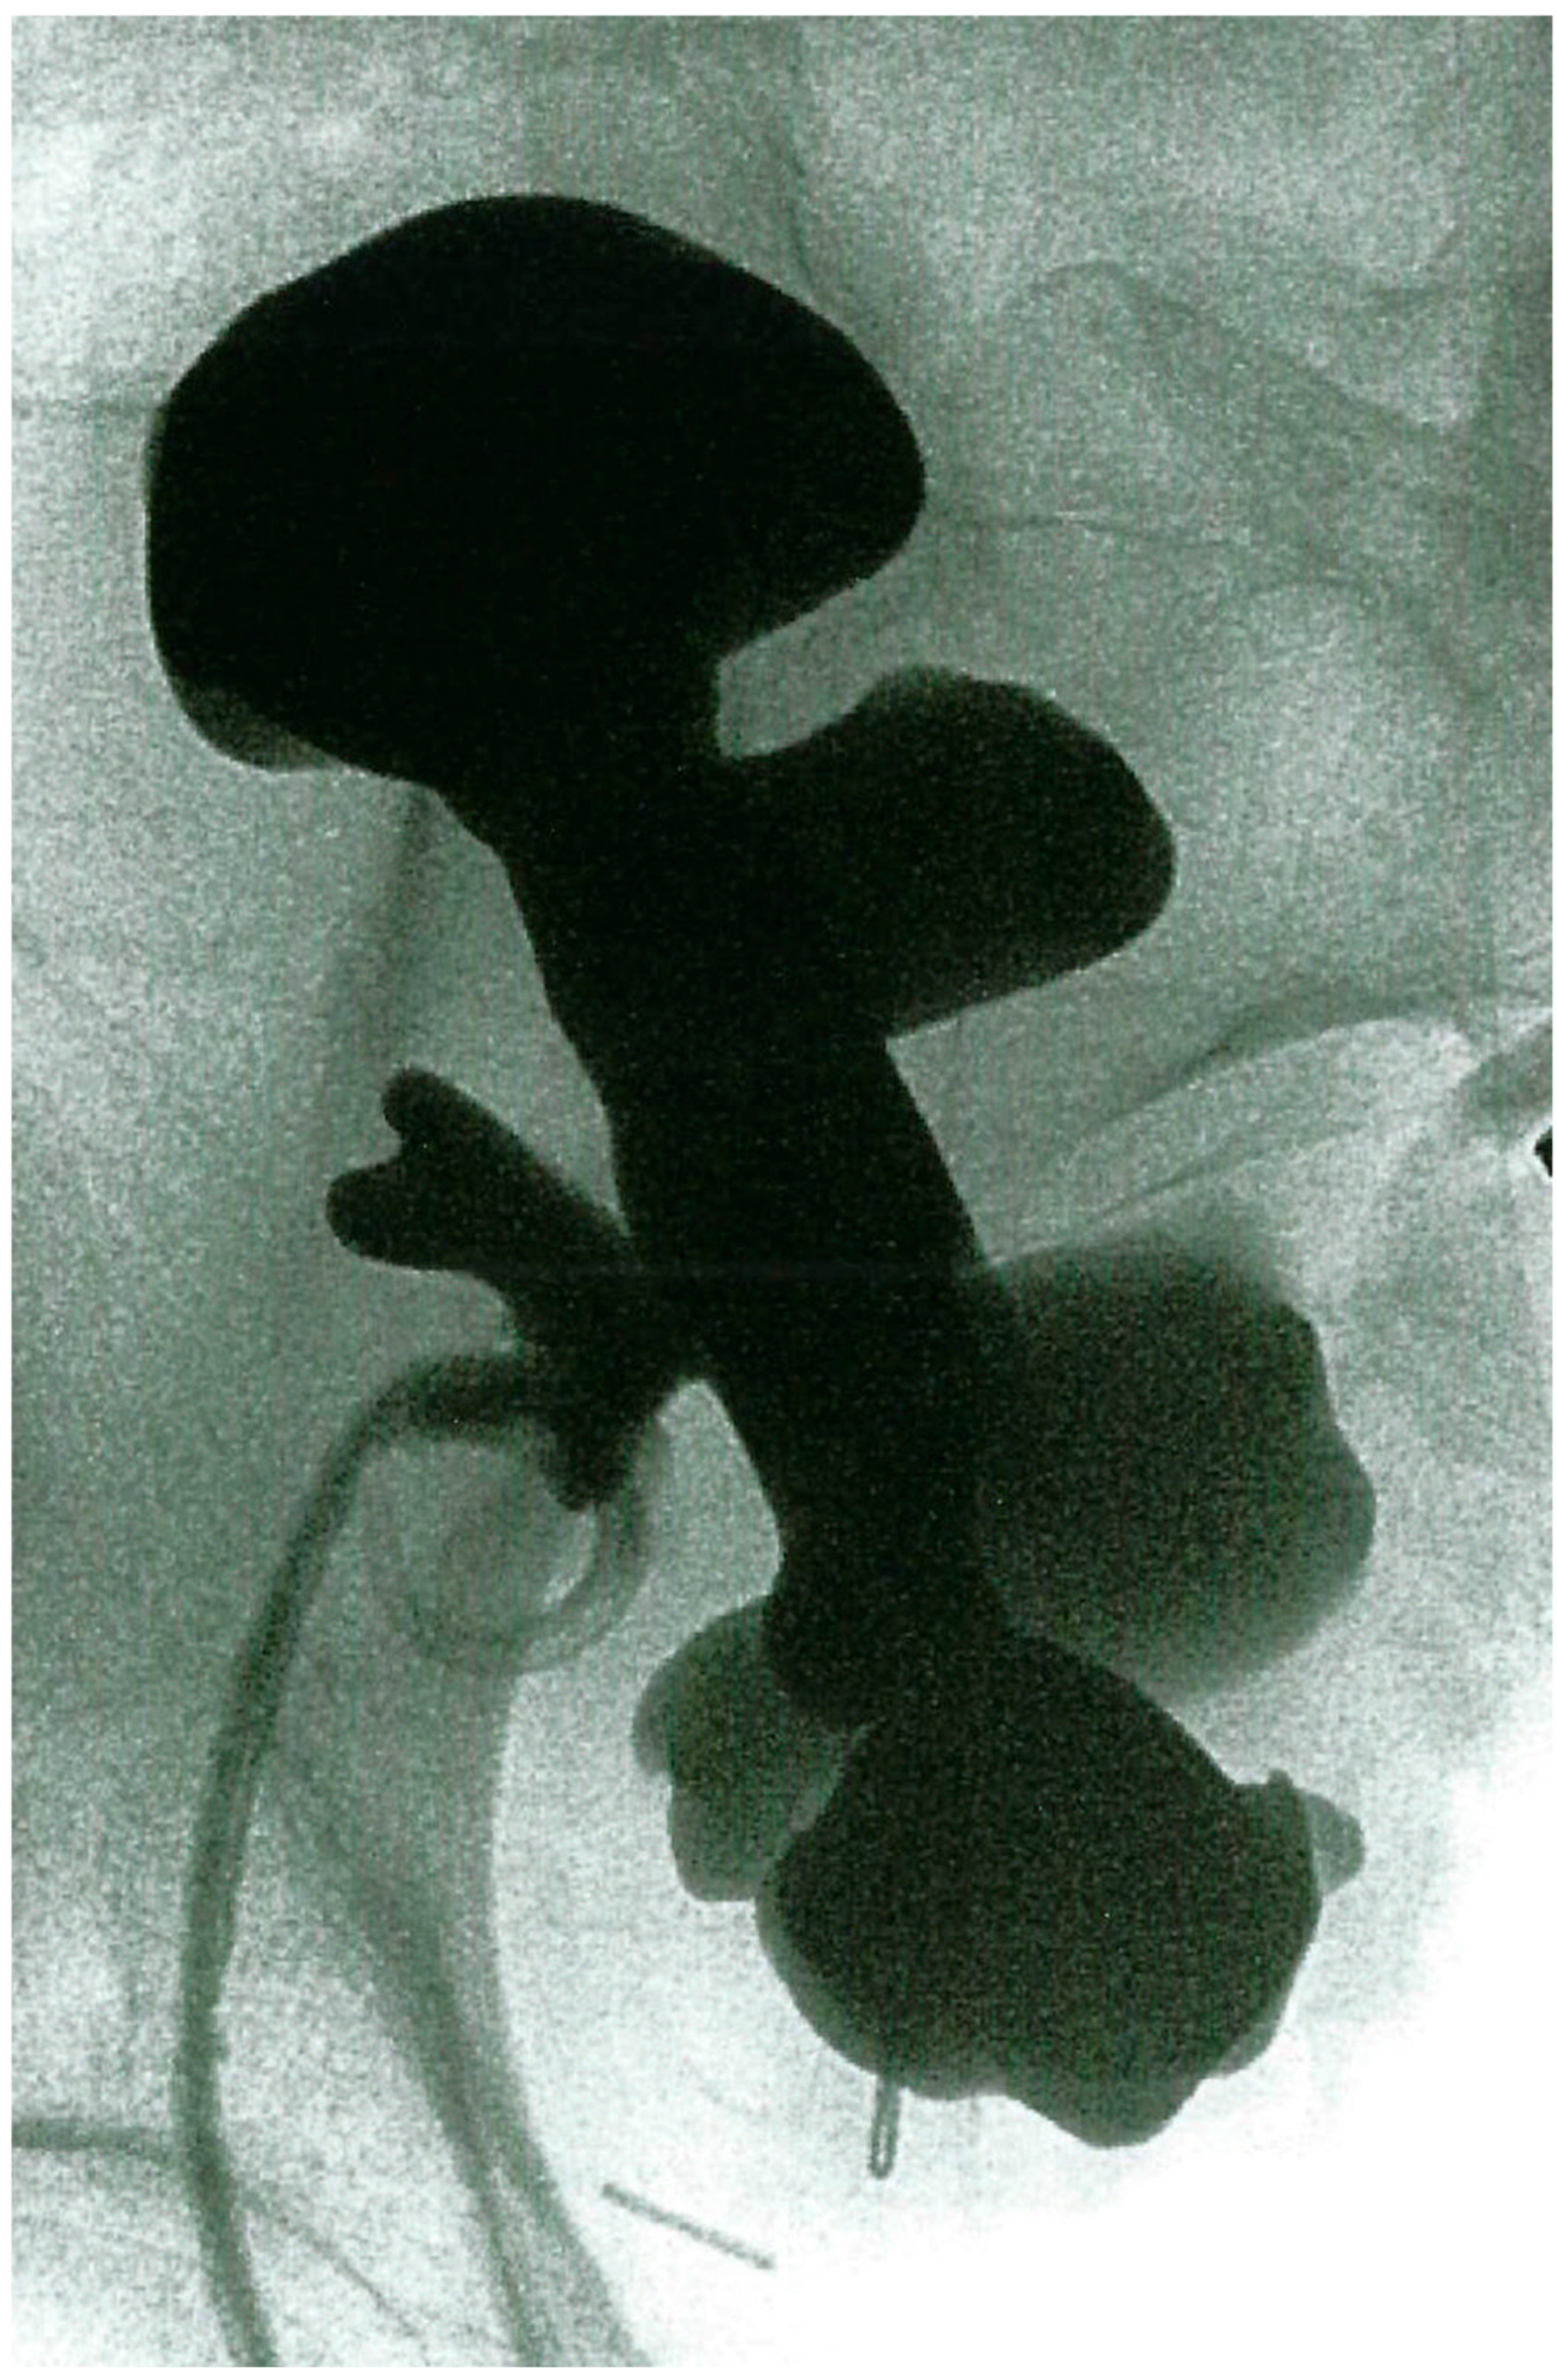

2.1. Case 1